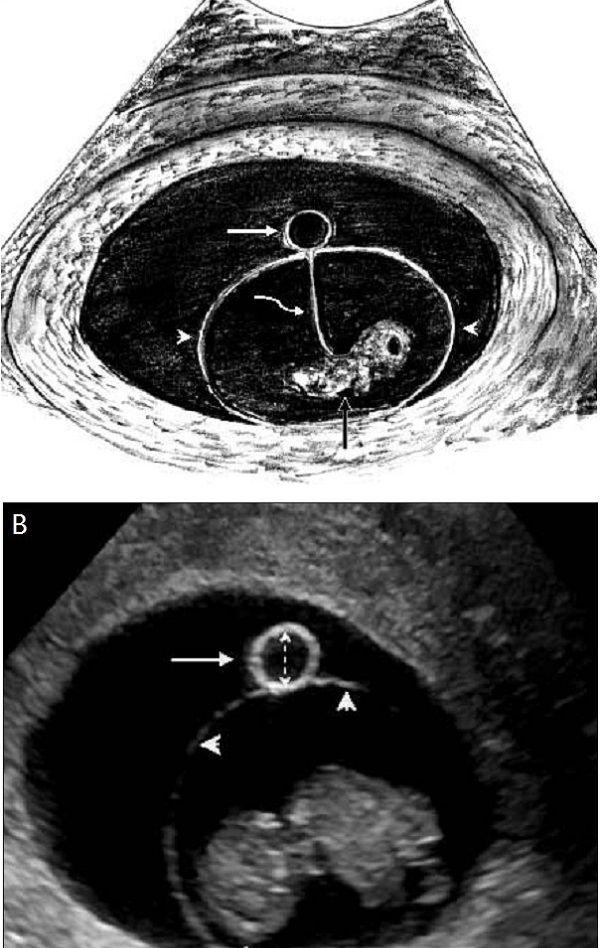

当孕囊平均直径在5-6mm时,通过阴道超声就可发现卵黄囊,正常来说,卵黄囊中央无回声,周边厚薄一致,边界清晰的环形高回声,具体如下图:

A图白色箭头显示妊娠囊内的正常卵黄囊,黑色箭头表示胚胎,在其中还可见羊膜、羊膜囊、绒毛膜囊和卵黄管等组织,B图为经阴道超声显示妊娠第9周的存活胚胎以及卵黄囊。